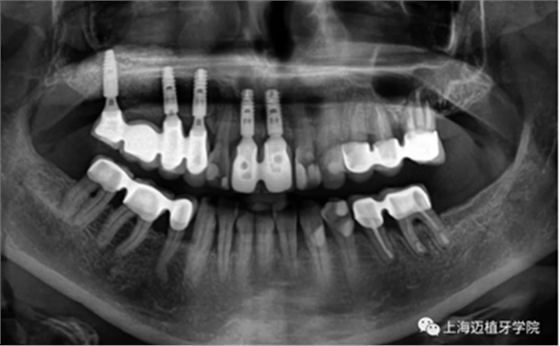

術后全景片,骨結合良好

術者:

Dr.Frank Zastrow

來源;上海邁植牙學院